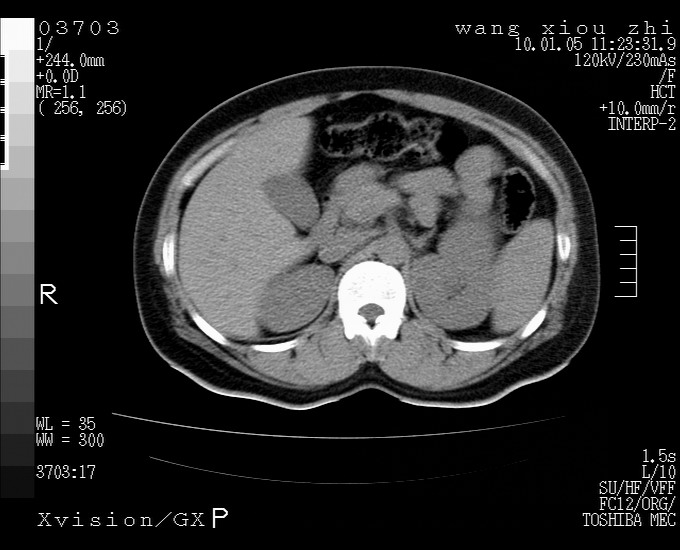

标题: CT23996:f,40.B超提示肿物。

左肾体积增大!下极见一密度略高团状软组织影!肾周结构组织未见明显异常!考虑左肾占位!建议增强!病史?

左肾占位性病变,建议增强。

左肾占位性病变,考虑肾癌,建议增强 。

左肾占位,肾门及腹膜后淋巴结肿大,考虑透明细胞癌可能性大,建议增强

左肾体积增大,内见肿块影,考虑占位,建议增强。